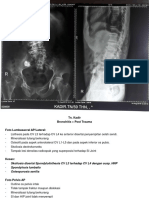

YTH TS :

Hasil pemeriksaan Foto Lumbo Sacral AP/Lateral:

- Alignment Lumbosacral intak, tidak tampak listhesis

- Osteofit pada aspek anterolateral CV L2-L5

- Discus dan foramen intervertebralis intak

- Jaringan lunak sekitarnya baik

Kesan : Spondylosis Lumbalis

Telah dilakukan Foto Lumbosacral AP/Lat dengan hasil sebagai berikut :

- Alignment tulang dan sendi lumbosacral kesan baik

- Tidak tampak fraktur, listhesis maupun dextruksi

- Tidak tampak osteofit CV lumbalis

- Celah sendi tidak menyempit

- Soft tissue sekitarnya baik

Kesimpulan : Foto lumbosacral dalam batas normal